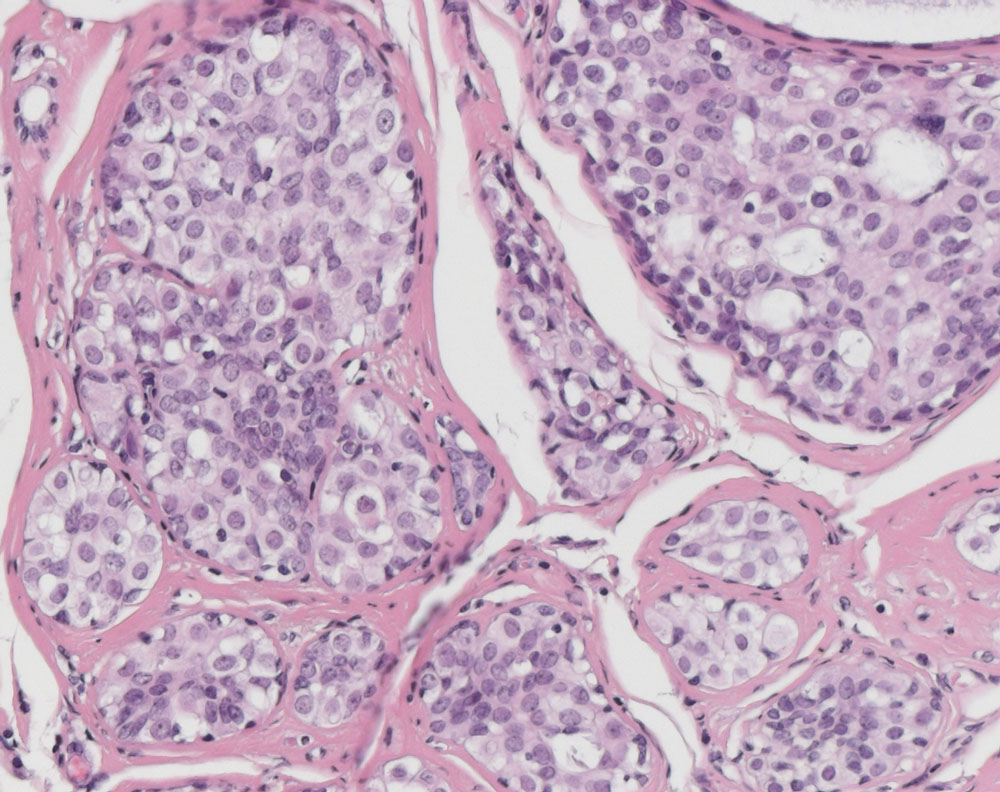

Un sarcome pléomorphe , appelé histocytofibrome malin jusqu'en 2002, est une tumeur des tissus mous de la famille des sarcomes. Il s'agit d'une tumeur agressive de croissance rapide, et qui atteint principalement le membre inférieur et la cuisse. Il peut être différencié en lipo- ou un fibro-sarcome, mais aussi indifférencié. La forme indifférenciée est la plus fréquente et représente 10 % de toutes les tumeurs des tissus mous, tandis que la forme liposarcomateuse est la plus rare.